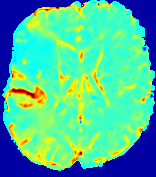

Slice #1Slice #2Slice #3Slice #4Slice #5Slice #6Dgtsuperscript𝐷gtD^{\text{gt}}Refer to captionRefer to captionRefer to captionRefer to captionRefer to captionRefer to captionDestsuperscript𝐷estD^{\text{est}}Refer to captionRefer to captionRefer to captionRefer to captionRefer to captionRefer to captionRefer to caption0.300.300.300.240.240.240.180.180.180.120.120.120.060.060.060.000.000.00(mm2/s)𝑚superscript𝑚2𝑠(mm^{2}/s)𝐕est𝟐subscriptnormsuperscript𝐕est2\|\bf{V}^{\text{est}}\|_{2}Refer to captionRefer to captionRefer to captionRefer to captionRefer to captionRefer to captionRefer to caption0.00300.00300.00300.00240.00240.00240.00180.00180.00180.00120.00120.00120.00060.00060.00060.00000.00000.0000(mm/s)𝑚𝑚𝑠(mm/s)

Figure 15: PIANO identifiability testing: diffusion imaging via advection-diffusion. Top row shows Dgtsuperscript𝐷gtD^{\text{gt}} used for simulating ground truth pure diffusion. Rows below show the estimated Destsuperscript𝐷estD^{\text{est}} and 𝐕est2subscriptnormsuperscript𝐕est2\|{\bf{V}}^{\text{est}}\|_{2} on corresponding slices. Note that the plotted value scale for 𝐕est2subscriptnormsuperscript𝐕est2\|{\bf{V}}^{\text{est}}\|_{2} is 0.01 of that for Dgtsuperscript𝐷gtD^{\text{gt}} and Destsuperscript𝐷estD^{\text{est}}.

Similarly, we test the behavior of PIANO when estimating both advection and diffusion from a pure diffusion-driven process. The goal is to determine if PIANO is able to recognize that there is only diffusion governing the given concentration time-series. We use the same ‘Diffusion Imaging’ data simulation of Sec. 4.2.1 as the concentration dataset, PIANO estimates both velocity 𝐕estsuperscript𝐕est{\bf{V}}^{\text{est}} and diffusivity Destsuperscript𝐷estD^{\text{est}}. Estimation results in Fig. 15 confirm PIANO’s identifiability again: the estimated 𝐕est2subscriptnormsuperscript𝐕est2\|{\bf{V}}^{\text{est}}\|_{2} is almost invisible compared to Destsuperscript𝐷estD^{\text{est}}, even plotted with a 1%percent11\% value range compared to that for Destsuperscript𝐷estD^{\text{est}}. On the other hand, Destsuperscript𝐷estD^{\text{est}} achieves comparable estimation performance as ‘Diffusion Imaging via Diffusion’ in which PIANO predicts Destsuperscript𝐷estD^{\text{est}} alone (shown in Fig. 13).